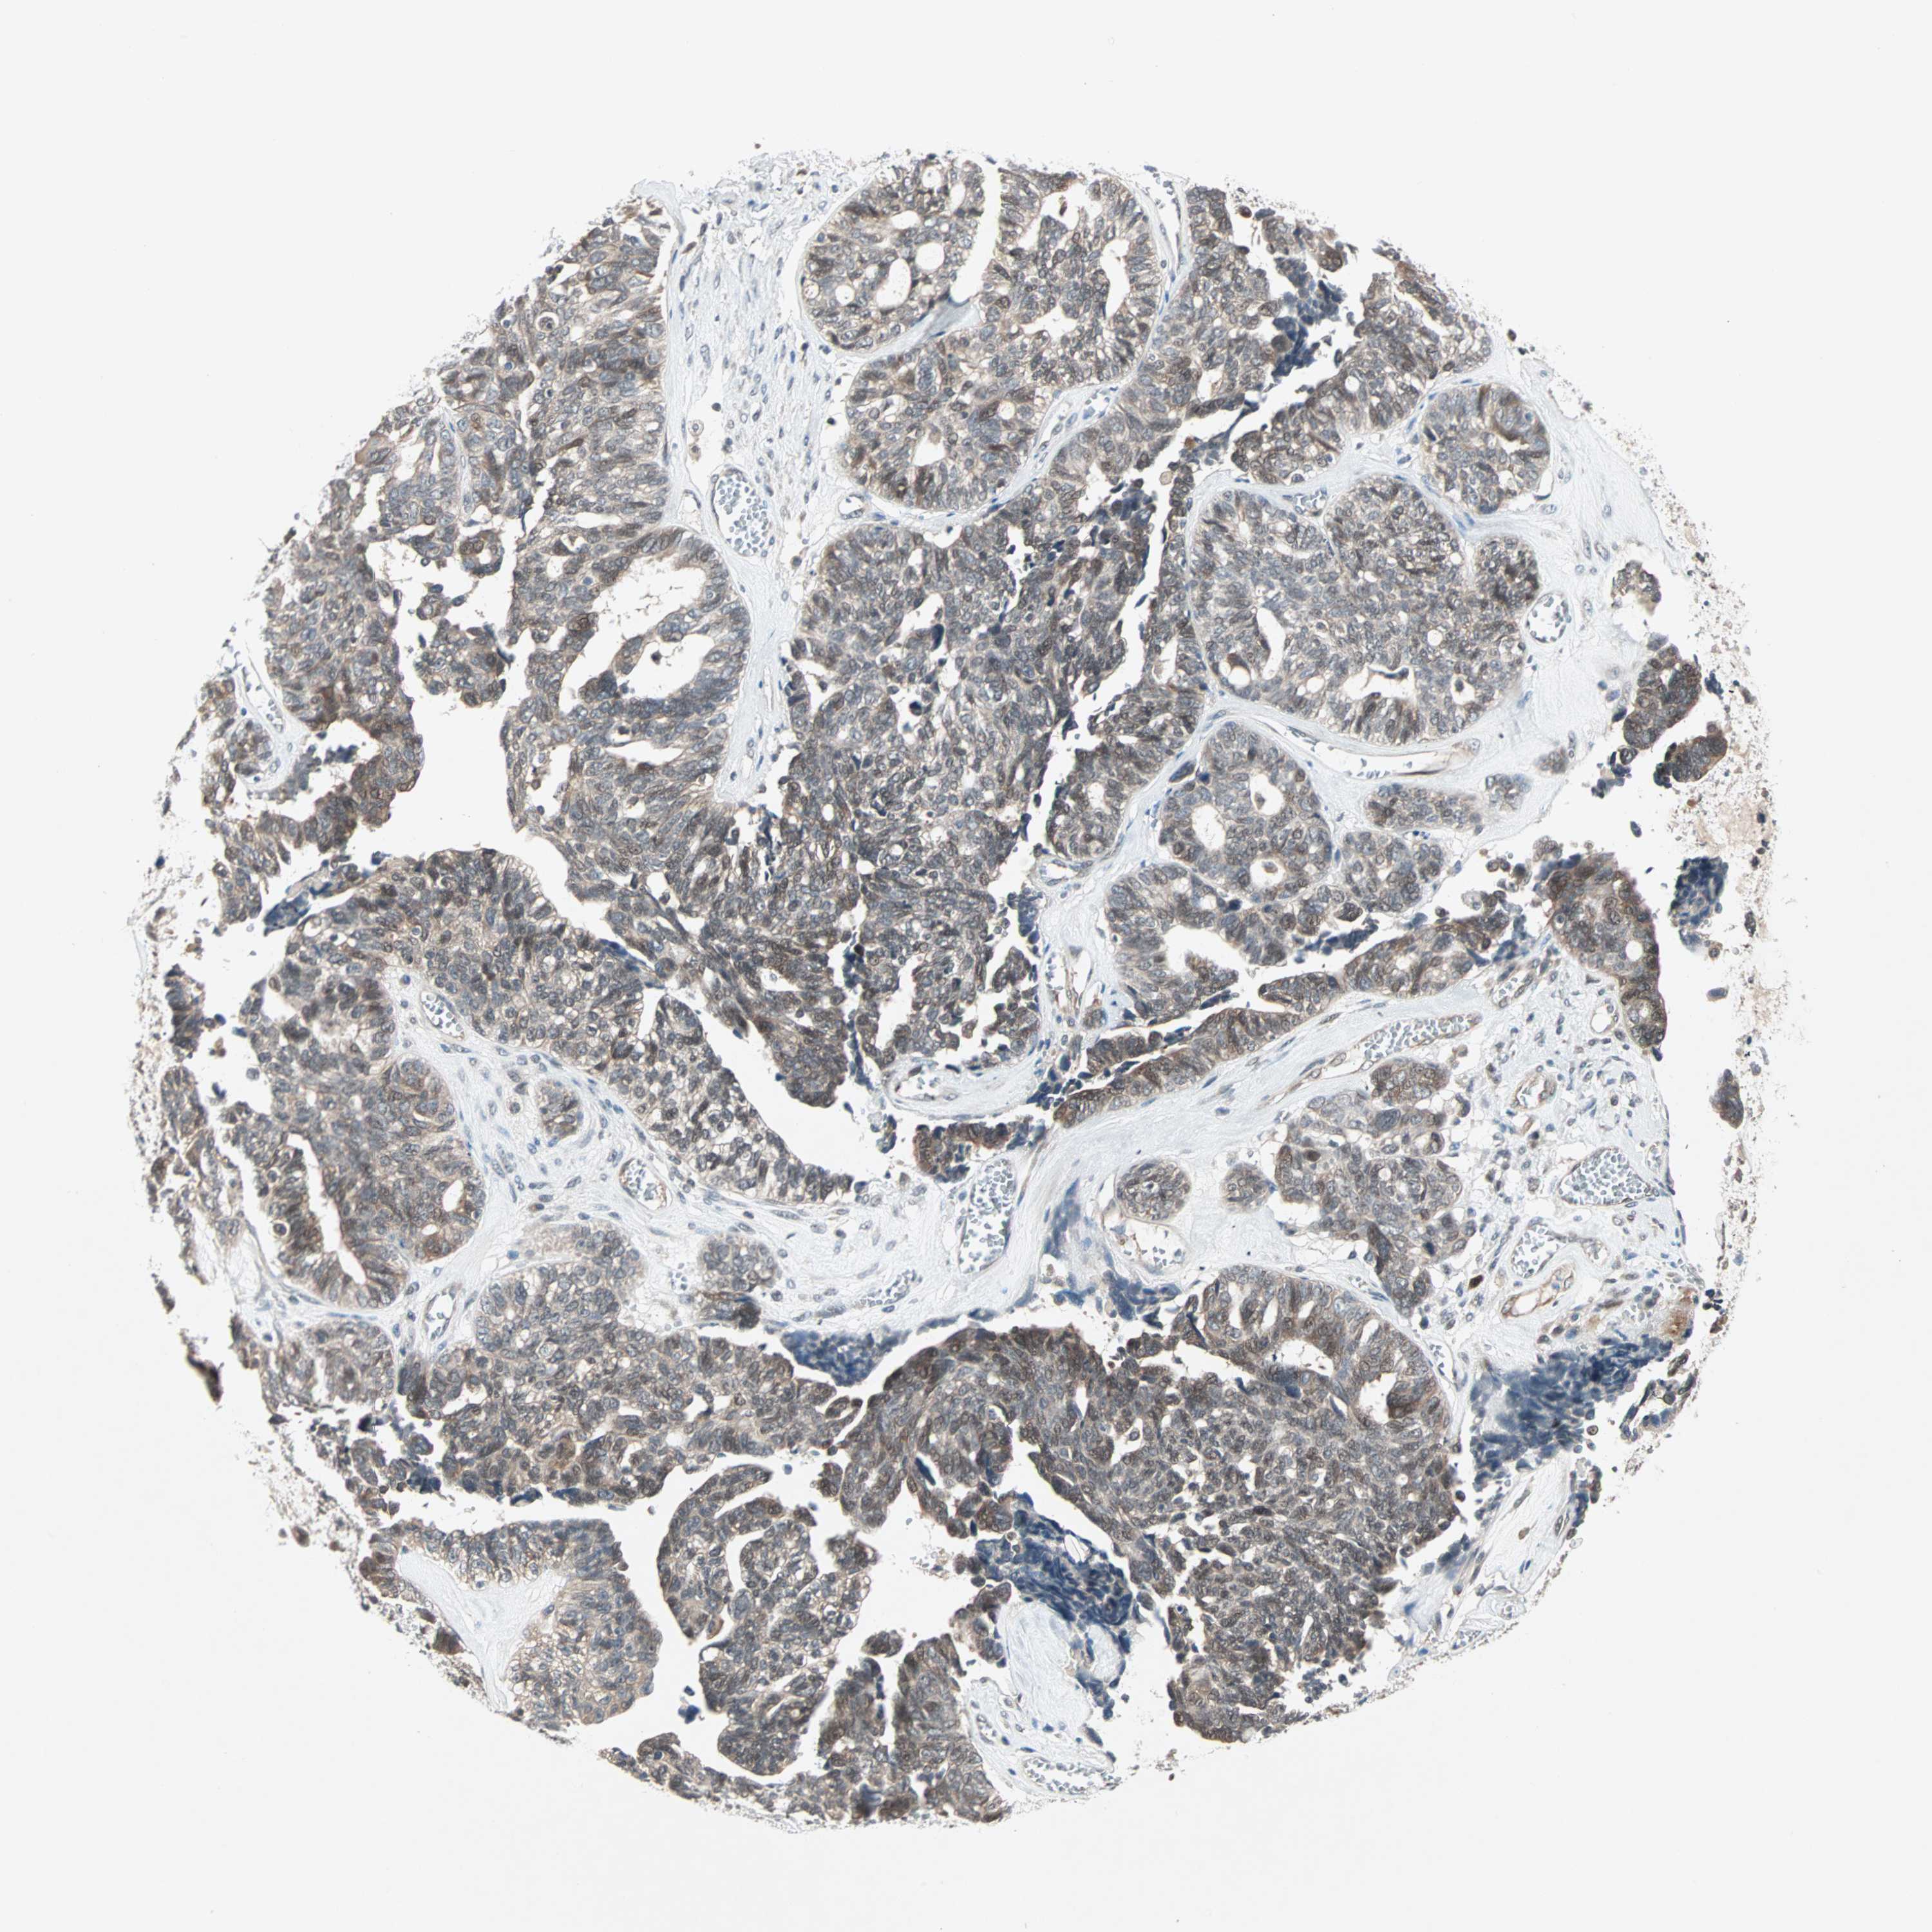

OVARIAN CANCER - Protein expressioni

A mouse-over function shows sample information and annotation data. Click on an image to view it in a full screen mode. Samples can be filtered based on level of antibody staining by selecting one or several of the following categories: high, medium, low and not detected. The assay and annotation is described here.

Note that samples used for immunohistochemistry by the Human Protein Atlas do not correspond to samples in the TCGA dataset.

Antibody stainingi

Antibody staining in the annotated cell types in the current human tissue is reported as not detected, low, medium, or high, based on conventional immunohistochemistry profiling in selected tissues. This score is based on the combination of the staining intensity and fraction of stained cells.

Each image is clickable and will lead to virtual microscopy that enables deeper exploration of all samples and also displays staining intensity scores, fraction scores and subcellular localization as well as patient and tissue information for each sample.

Antibody HPA007267

Staining

High

Medium

Low

Not detected

Intensity

Strong

Moderate

Weak

Negative

Quantity

>75%

75%-25%

<25%

None

Location

Nuclear

Cytoplasmic/membranous

Cytoplasmic/membranous,nuclear

Cystadenocarcinoma, serous, NOS

Carcinoma, endometroid

Cystadenocarcinoma, mucinous, NOS

Carcinoma, NOS